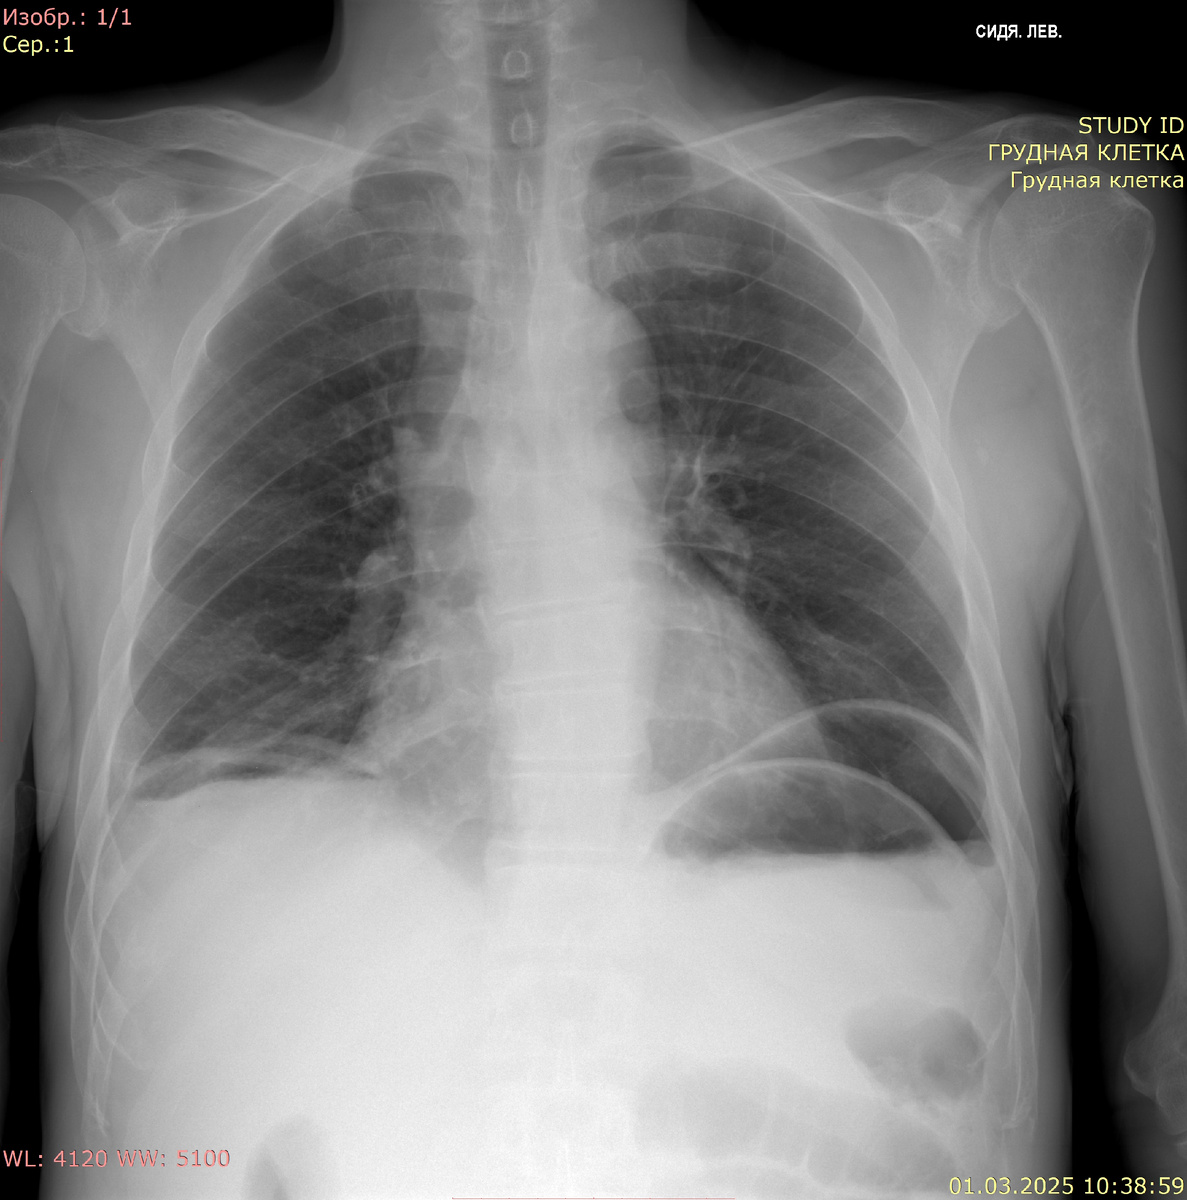

Рентгенография органов грудной клетки в прямой проекции:

Видимые дыхательные пути проходимы. Тень средостения не смещена, не расширена. Корни легких четкие, структурные, не расширены. Очаговых и инфильтративных изменений в легких нет. Синусы скрыты гомогенными горизонтальными тенями. Костно-деструктивных изменений нет. Свободный газ под куполами диафрагмы

Заключение: свободный газ в брюшной полости. Двусторонний минимальный плевральный выпот. Данных за очаговые или инфильтративные изменения не выявлено.